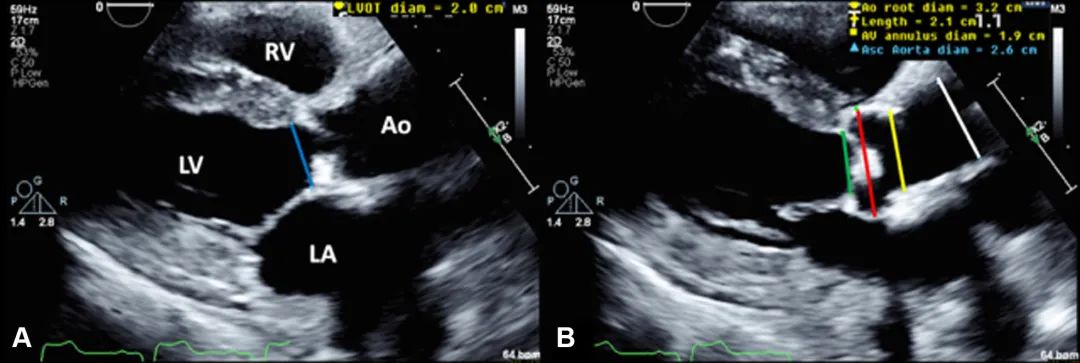

3、胸骨旁长轴切面:测量左室流出道(left ventricular outflow tract,LVOT)直径(于心脏收缩中期测量)、主动脉窦直径、主动脉瓣瓣环直径、窦管交界直径和升主动脉直径(图4)。

图4. 左室流出道和主动脉根部测量

胸骨旁长轴切面测量左室流出道直径(收缩中期测量;左图,蓝线)、主动脉瓣环直径(右图,绿线)、主动脉窦直径(右图,红线)、窦管交界直径(右图,黄线)和升主动脉直径(右图,白线)。缩写同图2。